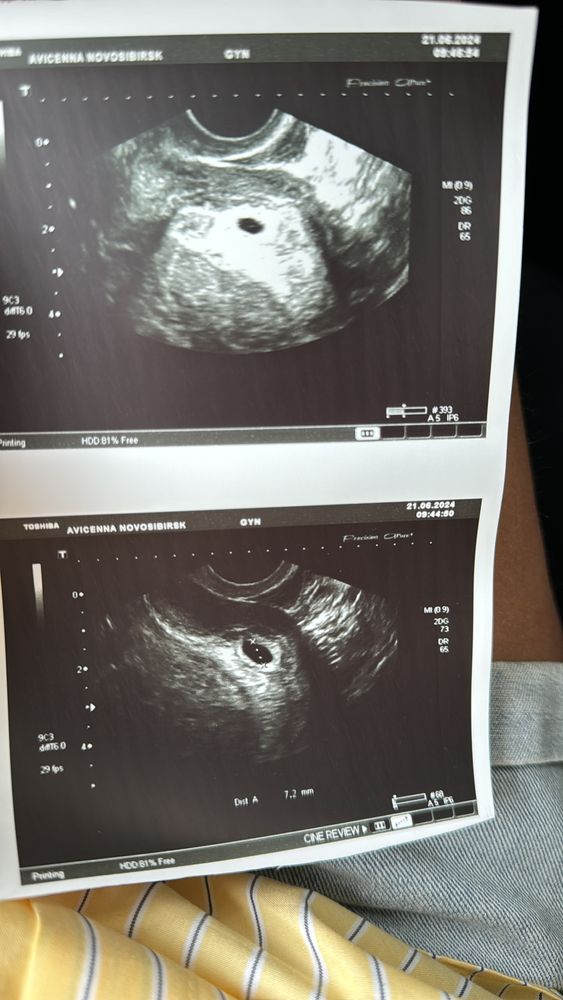

18 дпп, нет желточного мешка. У кого так было? Поделитесь размерами плодного яйца

В ПЯ 7мм сложно что-то разглядеть. Самое главное, что ПЯ есть, и оно в матке) Остальное чуть позже) Уменя на 18дпп ПЯ было 10мм и 2мм ЖМ. Но у меня всю беременность опережало развитие.

Евгения , там еще от аппарата зависит и от ре. Вам фотку дали? Посмотрите внимательномне кажется жм в уголке у меня был, я ре показала она сказала не видит ничего😬. В любом случае еще рано, все будет Изображение

Ирина, вот так) Изображение

Евгения , мне кажется у вас тоже в уголочке сверху на втором фото что-то есть😊